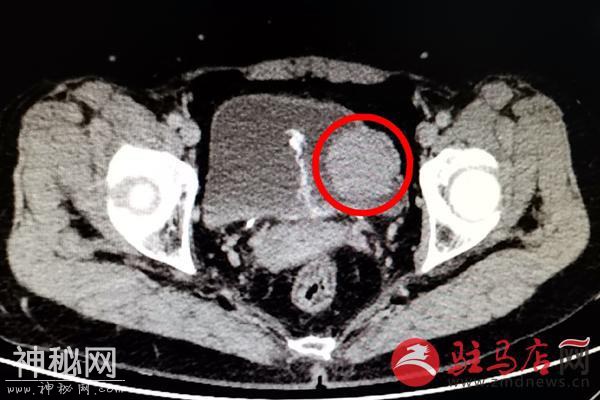

近日,张女士的这个“怪病”终于在驻马店市中心医院泌尿外二科治好了,原来,张女士的膀胱里长了一个鸡蛋大小的肿瘤,叫嗜铬细胞瘤,经过手术,切除了瘤体,张女士的血压终于恢复正常了。

8月上旬,她在本县医院全身体检时,竟发现膀胱有肿物,随即来驻马店市中心医院泌尿外科就诊, 据接诊医生黄雪强说:“入院后患者排尿时血压高压达到220mmHg,并且伴有头晕、心慌、下腹不适的症状。泌尿系CT检查,发现膀胱占位病变。”

经过充分的术前准备,扩容,监测控制血压后,于8月24日在全麻下行膀胱部分切除术。手术中患者血压波动剧烈,最高压达到251/124mmHg,最低血压90/60mmHg,随时有生命危险,主刀医生文秀华、刘太阳凭借精湛的技术,在麻醉医师王震、手术室护士刘鹏、陈亚青等医护人员的密切配合下,完整将膀胱内直径约5cm的瘤体切除。术后患者ICU观察后生命体征平稳后转入普通病房,目前患者恢复良好,血压完全恢复正常。